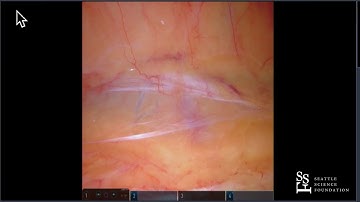

02 Robotic Partial Nephrectomy Course Tips for retroperitoneal partial nephrectomy James Porter HD